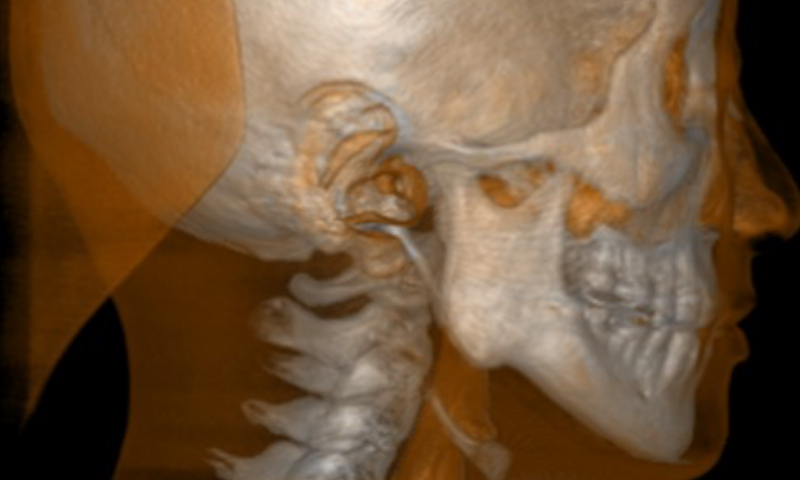

高画質3Dレントゲン最先端のレントゲン技術で、さらに正確な診断を実現

当院では、患者様に優しく、正確な診断を行うことができる最先端レントゲン、スキャニング機器「カボ OP 3D ビジョン」を導入しています。

低い被ばく線量と精密な360度高画質スキャニングが特徴で、当院でもこだわりの院内設備となっております。